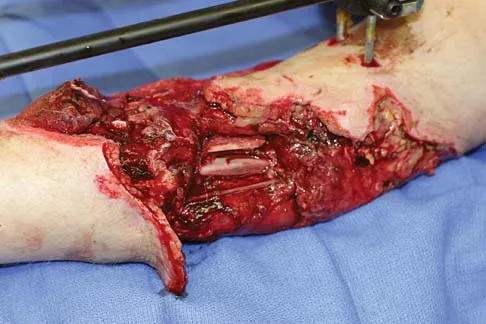

A 37-year-old man pulled his hamstring playing softball 3 weeks ago. The patient had not noted any mass prior to his injury. MRI scans of the posterior thigh are shown in Figures 4a and 4b. Figure 4c shows the biopsy specimen from a needle biopsy. What is the most likely diagnosis?

Explanation